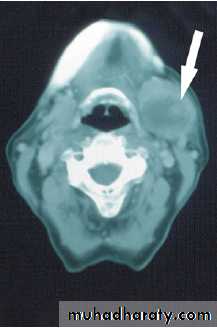

1-Computed tomography (CT) and MRI scanning

the extension, circumscribed (benign, or diffuse, invasive and probably malignant).2- Biopsy

- The parotid gland is the most common site for salivary tumors.

Most tumors arise in the superficial lobe80–90 % of tumours of the parotid gland are benign

Slow growing, painless swellings below the ear, in front of the ear or in the upper aspect of the neck.

- Less commonly, tumors in accessory lobe persistent swellings in the cheek.

- Rarely, tumours in deep lobe as parapharyngeal massesdifficulty in swallowing and snoring.